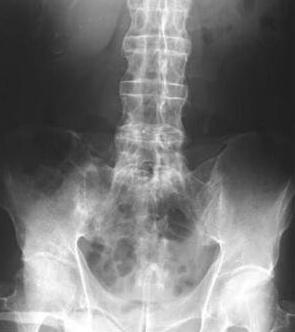

张先生因没日没夜的打游戏,长期保持不正确的坐姿患上强直性脊柱炎,此后肩膀处疼痛难忍,手指僵硬,胯关节处开始疼痛,坐都不能坐了,走路受到限制。长久延误治疗后导致脊柱已有轻微的变形,经药物治疗后病情反复复发,最后在家人的陪伴下来到我院接受治疗。

(图:张先生初到院时脊柱变形情况)